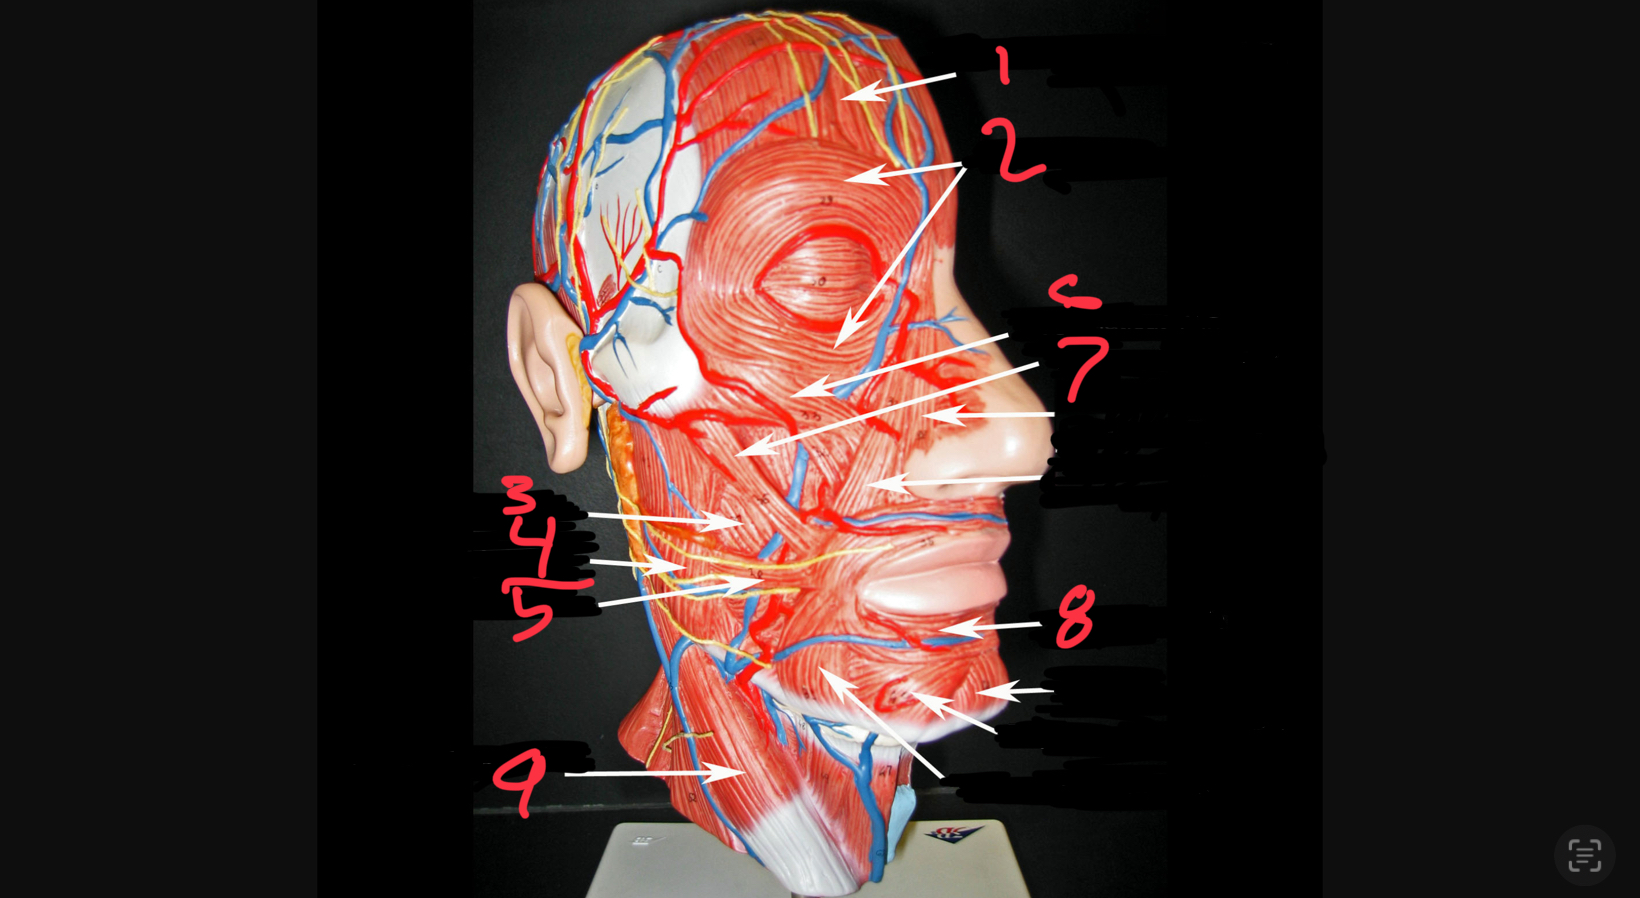

what #1

occipitofrontalis (frontal belly)

what is #2

orbicularis oculi

what is #3

buccinator

what is #4

masseter

what is #5

risorius

what is #6

zygomaticus minor

what is #7

zygomaticus major

what is #8

orbicularis oris

what is #9

sternocleidomastoid